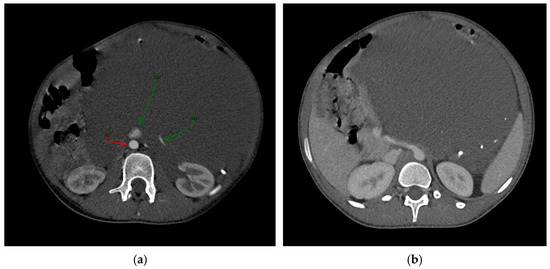

An ultrasound examination was performed with the visualization of a multiloculated lesion, characterized by anechoic and hypoechoic cystic spaces separated by thin septations, with moderate intralesional vascularization observed after color Doppler evaluation. Then, a second-level imaging with contrast-enhanced CT scan of the abdomen was performed, revealing an intraperitoneal large, multiseptated hypodense mass containing multiple calcified components (Figure 1), measuring approximately 21 × 16 cm in the axial plane and extending up to 30 cm in the sagittal plane. The lesion occupied nearly the entire abdominal cavity, predominantly on the left side, compressing adjacent structures. It wrapped smoothly around the left kidney and adrenal gland, displacing bowel loops and other abdominal organs, with a poorly defined interface with the surrounding tissues.

The major abdominal vessels, including the celiac trunk, superior mesenteric artery, inferior mesenteric artery, and the inferior vena cava, as well as both renal veins and arteries, were compressed with a partial course within the mass itself. However, no evidence of vascular compromise was observed.

On CT imaging, LVMs typically appear as cystic lesions that may be unilocular or multilocular with internal septations. They usually show fluid attenuation, while the walls and septa often demonstrate contrast enhancement. In some cases, calcifications can be observed, a finding that may also occur in teratomas, as in our case [3].

Figure 1. The axial post-contrast CT in the arterious (a) and portovenous (b) phase reveals the full extent of the mass and its intra-peritoneal location, without infiltration of the adjacent structures. The mass contains calcified density components, which were later identified as phleboliths. (a): Green arrows indicated the Renal Vein (RV) and Inferior Vena Cava (ICV); red arrow indicated the Aorta (AO).